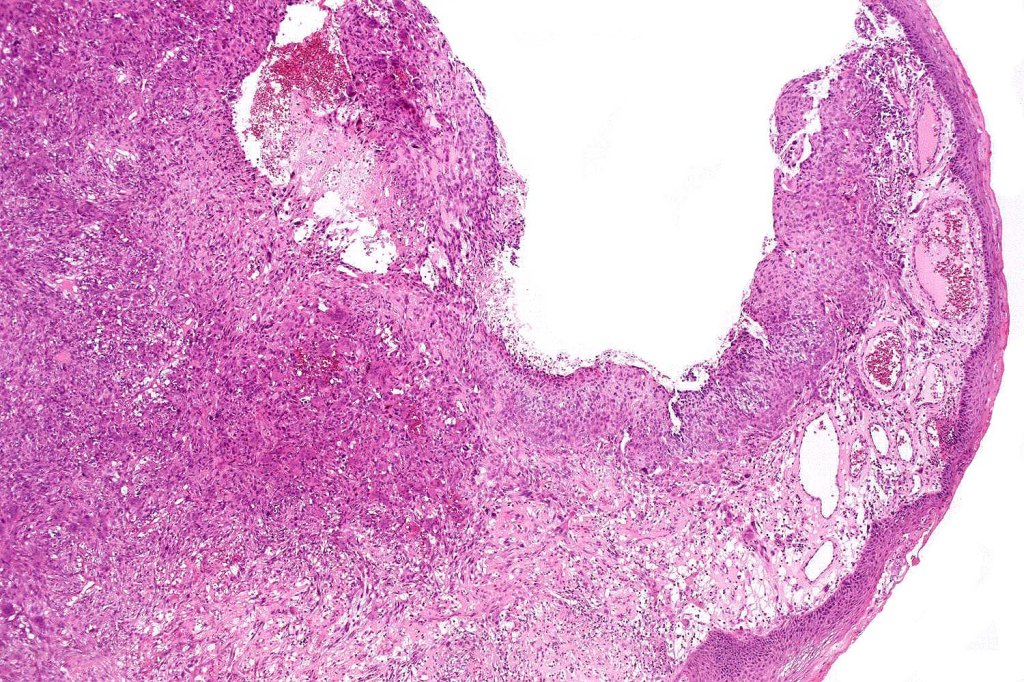

Carcinosarcoma

Cutaneous carcinosarcoma (metaplastic carcinoma, carcinoma with heterologous differentiation)

Histological features

•Osteoid

•Chondroid

•Smooth muscle

•MFH-like features with osteoclasts

•Neural differentiation